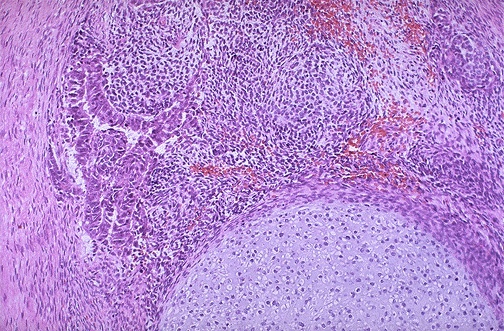

At the bottom is a focus of cartilage. Above this is a primitive mesenchymal stroma and to the left a focus of primitive cells most characteristic for embryonal carcinoma. This is embryonal carcinoma mixed with teratoma.